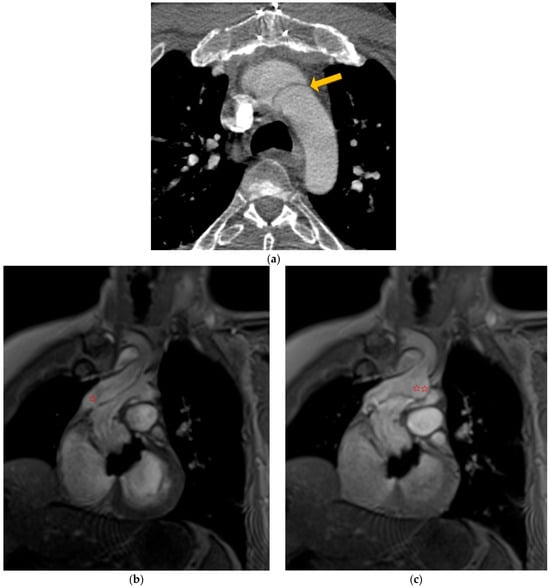

In this context, dynamic magnetic resonance imaging angiography of the aorta showed complete occlusion of the aortic arch downstream of the innominate artery by the residual intimal flap (Figure 5a, arrow). This confirmed the diagnostic hypothesis of intermittent aortic occlusion (Figure 5b,c and Video S1).

Figure 5.

Computed tomography angiography (yellow arrow shows residual intimal flap (a) and flow MRI (b,c) showing a tear in the residual flap (✩) leading to a picture of transient obstruction of the aortic arch; MIR reconstruction (✩✩)—video on annexe.